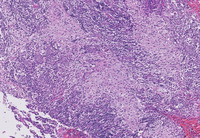

Figure 1-H&E

The low power H&E image demonstrates multifocal pale eosinophilic areas and higher power demonstrates that these pale areas comprise accumulations of large bland histiocytes with abundant pale eosinophilic cytoplasm with intermingled lymphocytes and plasma cells.  Higher power demonstrates that these histiocytes have small but distinct nucleoli.